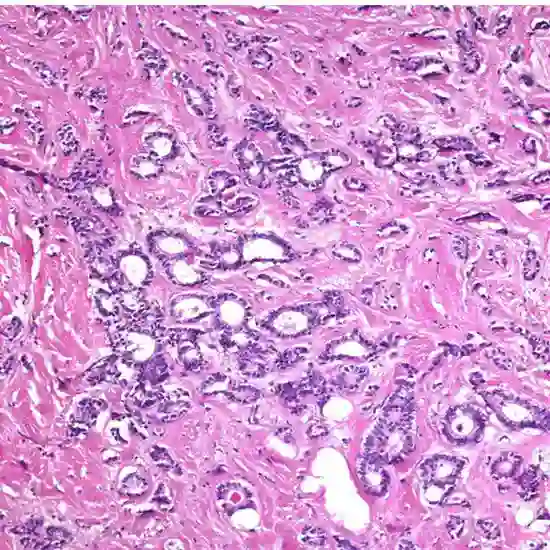

Tubular Carcinoma is characterized by small, well-defined tubules (tiny microscopic tube-like structures) formed by cancer cells that invade the surrounding breast tissue. These structures are typically well-differentiated, meaning that the cancer cells are more similar in appearance to other types of breast cancer.